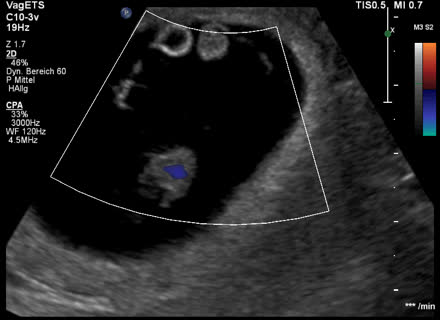

Zwillinge 9 SSW Hallo liebe Experten, ich bin heute bei rechnerisch und wir waren beim Ultraschall Man konnte beide Fruchthöhle mit den Babys sehen (zweieiig, jedes isst vom eigenem Tellerchen meinte die Ärztin) Beide Herzen schlagen und sie sind gleich Eineiige Zwillinge werden in der Medizin auch monozygote Zwillinge genannt. Sie sind im 7 Monat angekommen, in Schwangerschaftswoche 27 (SSW 27 06) In dieser Woche öffnen Ihre Zwillinge erstmals ihre Augen. Ultraschall 7 SSW Links in der Fruchtblase ist der etwa fünf Millimeter lange, wie eine Bohne gekrümmte Embryo sichtbar Der helle Kreis mit dunklem Fleck über dem Embryo ist der Dottersack, der den Embryo momentan noch mit Nährstoffen versorgt, bis die Plazenta diese Aufgabe voll übernehmen kann.